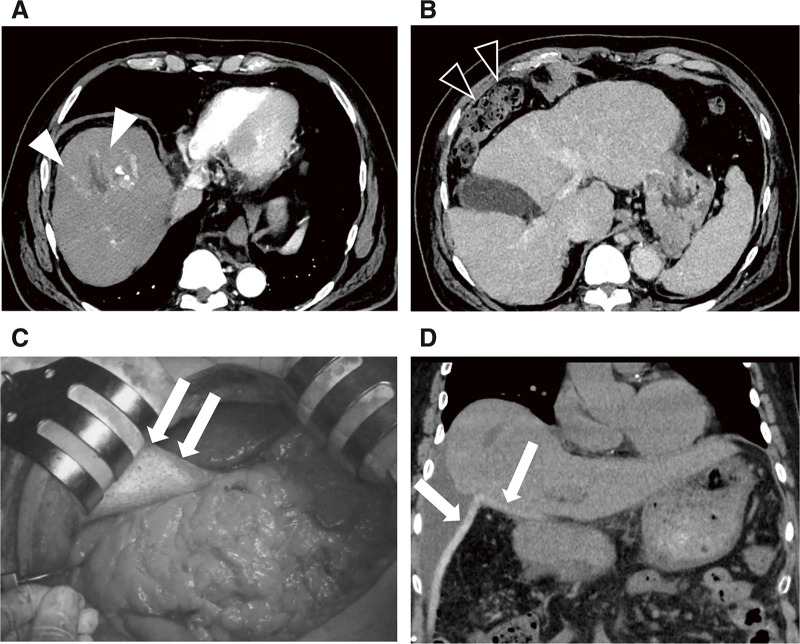

Case presentation: We report the case of a 77-year-old male patient diagnosed with a 6 cm HCC in segment 8, accompanied by impaired liver function, precluding hepatic resection. PBT was planned; however, because of the proximity of the gastrointestinal tract to the tumor, spacer placement was deemed necessary, and a bioabsorbable polyglycolic acid spacer was placed, followed by PBT. Owing to the sufficient space provided by the spacer, curative doses of PBT could be delivered to the tumor, and the patient survived for 26 months after spacer placement surgery without any sign of recurrence.